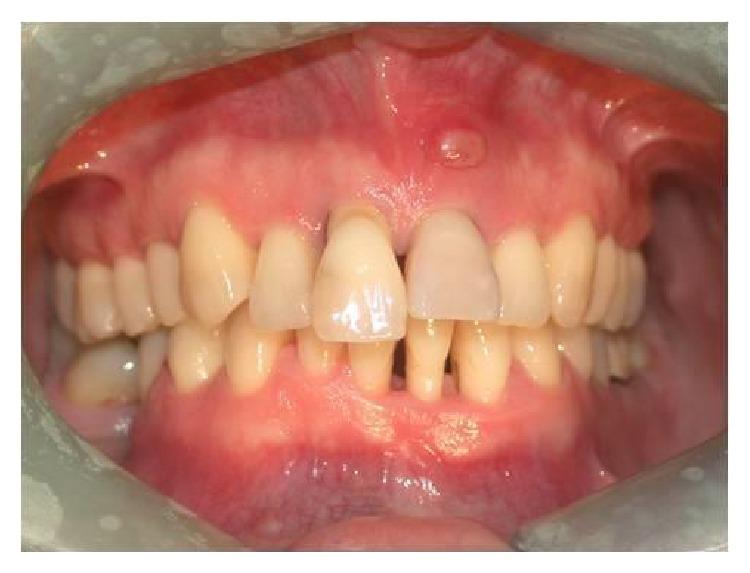

The functional and aesthetic restoration of teeth compromised due to aggressive periodontitis presents numerous challenges for the clinician. Horizontal bone loss and soft tissue destruction resulting from periodontitis can impede implant placement and the regeneration of an aesthetically pleasing gingival smile line, often requiring bone augmentation and mucogingival surgery, respectively. Conservative approaches to the treatment of aggressive periodontitis (i.e., treatments that use minimally invasive tools and techniques) have been purported to yield positive outcomes. Here, we report on the treatment and five-year follow-up of patient suffering from aggressive periodontitis using a minimally invasive surgical technique and implant system. By using the methods described herein, we were able to achieve the immediate aesthetic and functional restoration of the maxillary incisors in a case that would otherwise require bone augmentation and extensive mucogingival surgery. This technique represents a conservative and efficacious alternative to the aesthetic and functional replacement of teeth compromised due to aggressive periodontitis.

侵袭性牙周炎导致牙齿功能和美观受损,给临床医生带来诸多挑战。牙周炎引起的水平骨吸收和软组织破坏会妨碍种植体植入以及美观的牙龈微笑线的再生,通常分别需要进行骨增量和膜龈手术。据称,侵袭性牙周炎的保守治疗方法(即使用微创工具和技术的治疗方法)能产生积极效果。在此,我们报告了一名侵袭性牙周炎患者采用微创外科技术和种植系统的治疗及五年随访情况。通过使用本文所述方法,在原本需要骨增量和广泛膜龈手术的病例中,我们成功实现了上颌切牙的即刻美观和功能恢复。该技术是侵袭性牙周炎导致牙齿功能和美观受损时,一种保守且有效的替代治疗方法。